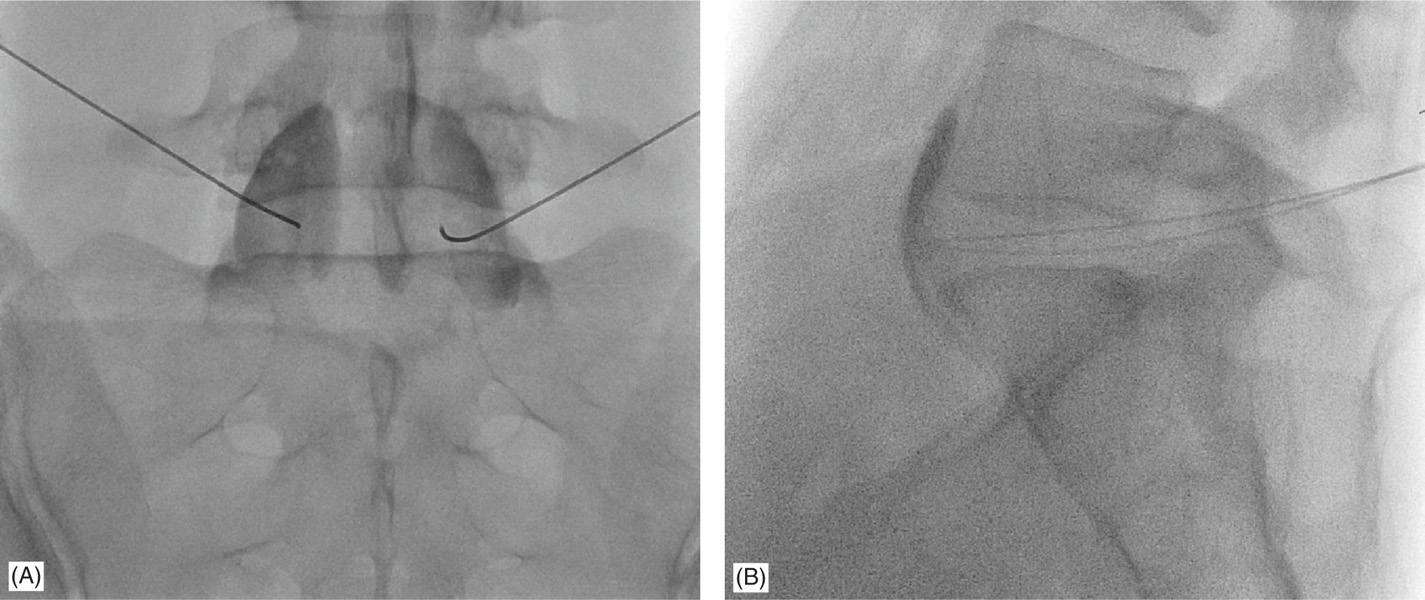

Technique for Superior Hypogastric Plexus Block

• The patient lies down on belly in the operating room.

• Needle insertion points are marked with the help of fluoroscopy (X-ray).

• After local anesthesia, needles are advanced.

• Correct placement is confirmed with contrast spread in the midline region.

• Once the needles are placed correctly local anaesthetic with or without steroid is injected.